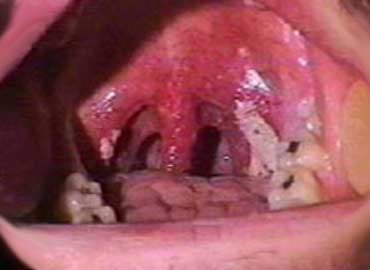

Фото Симптомы острого фарингита Фото Симптомы острого фарингита

Фото Симптомы острого фарингита